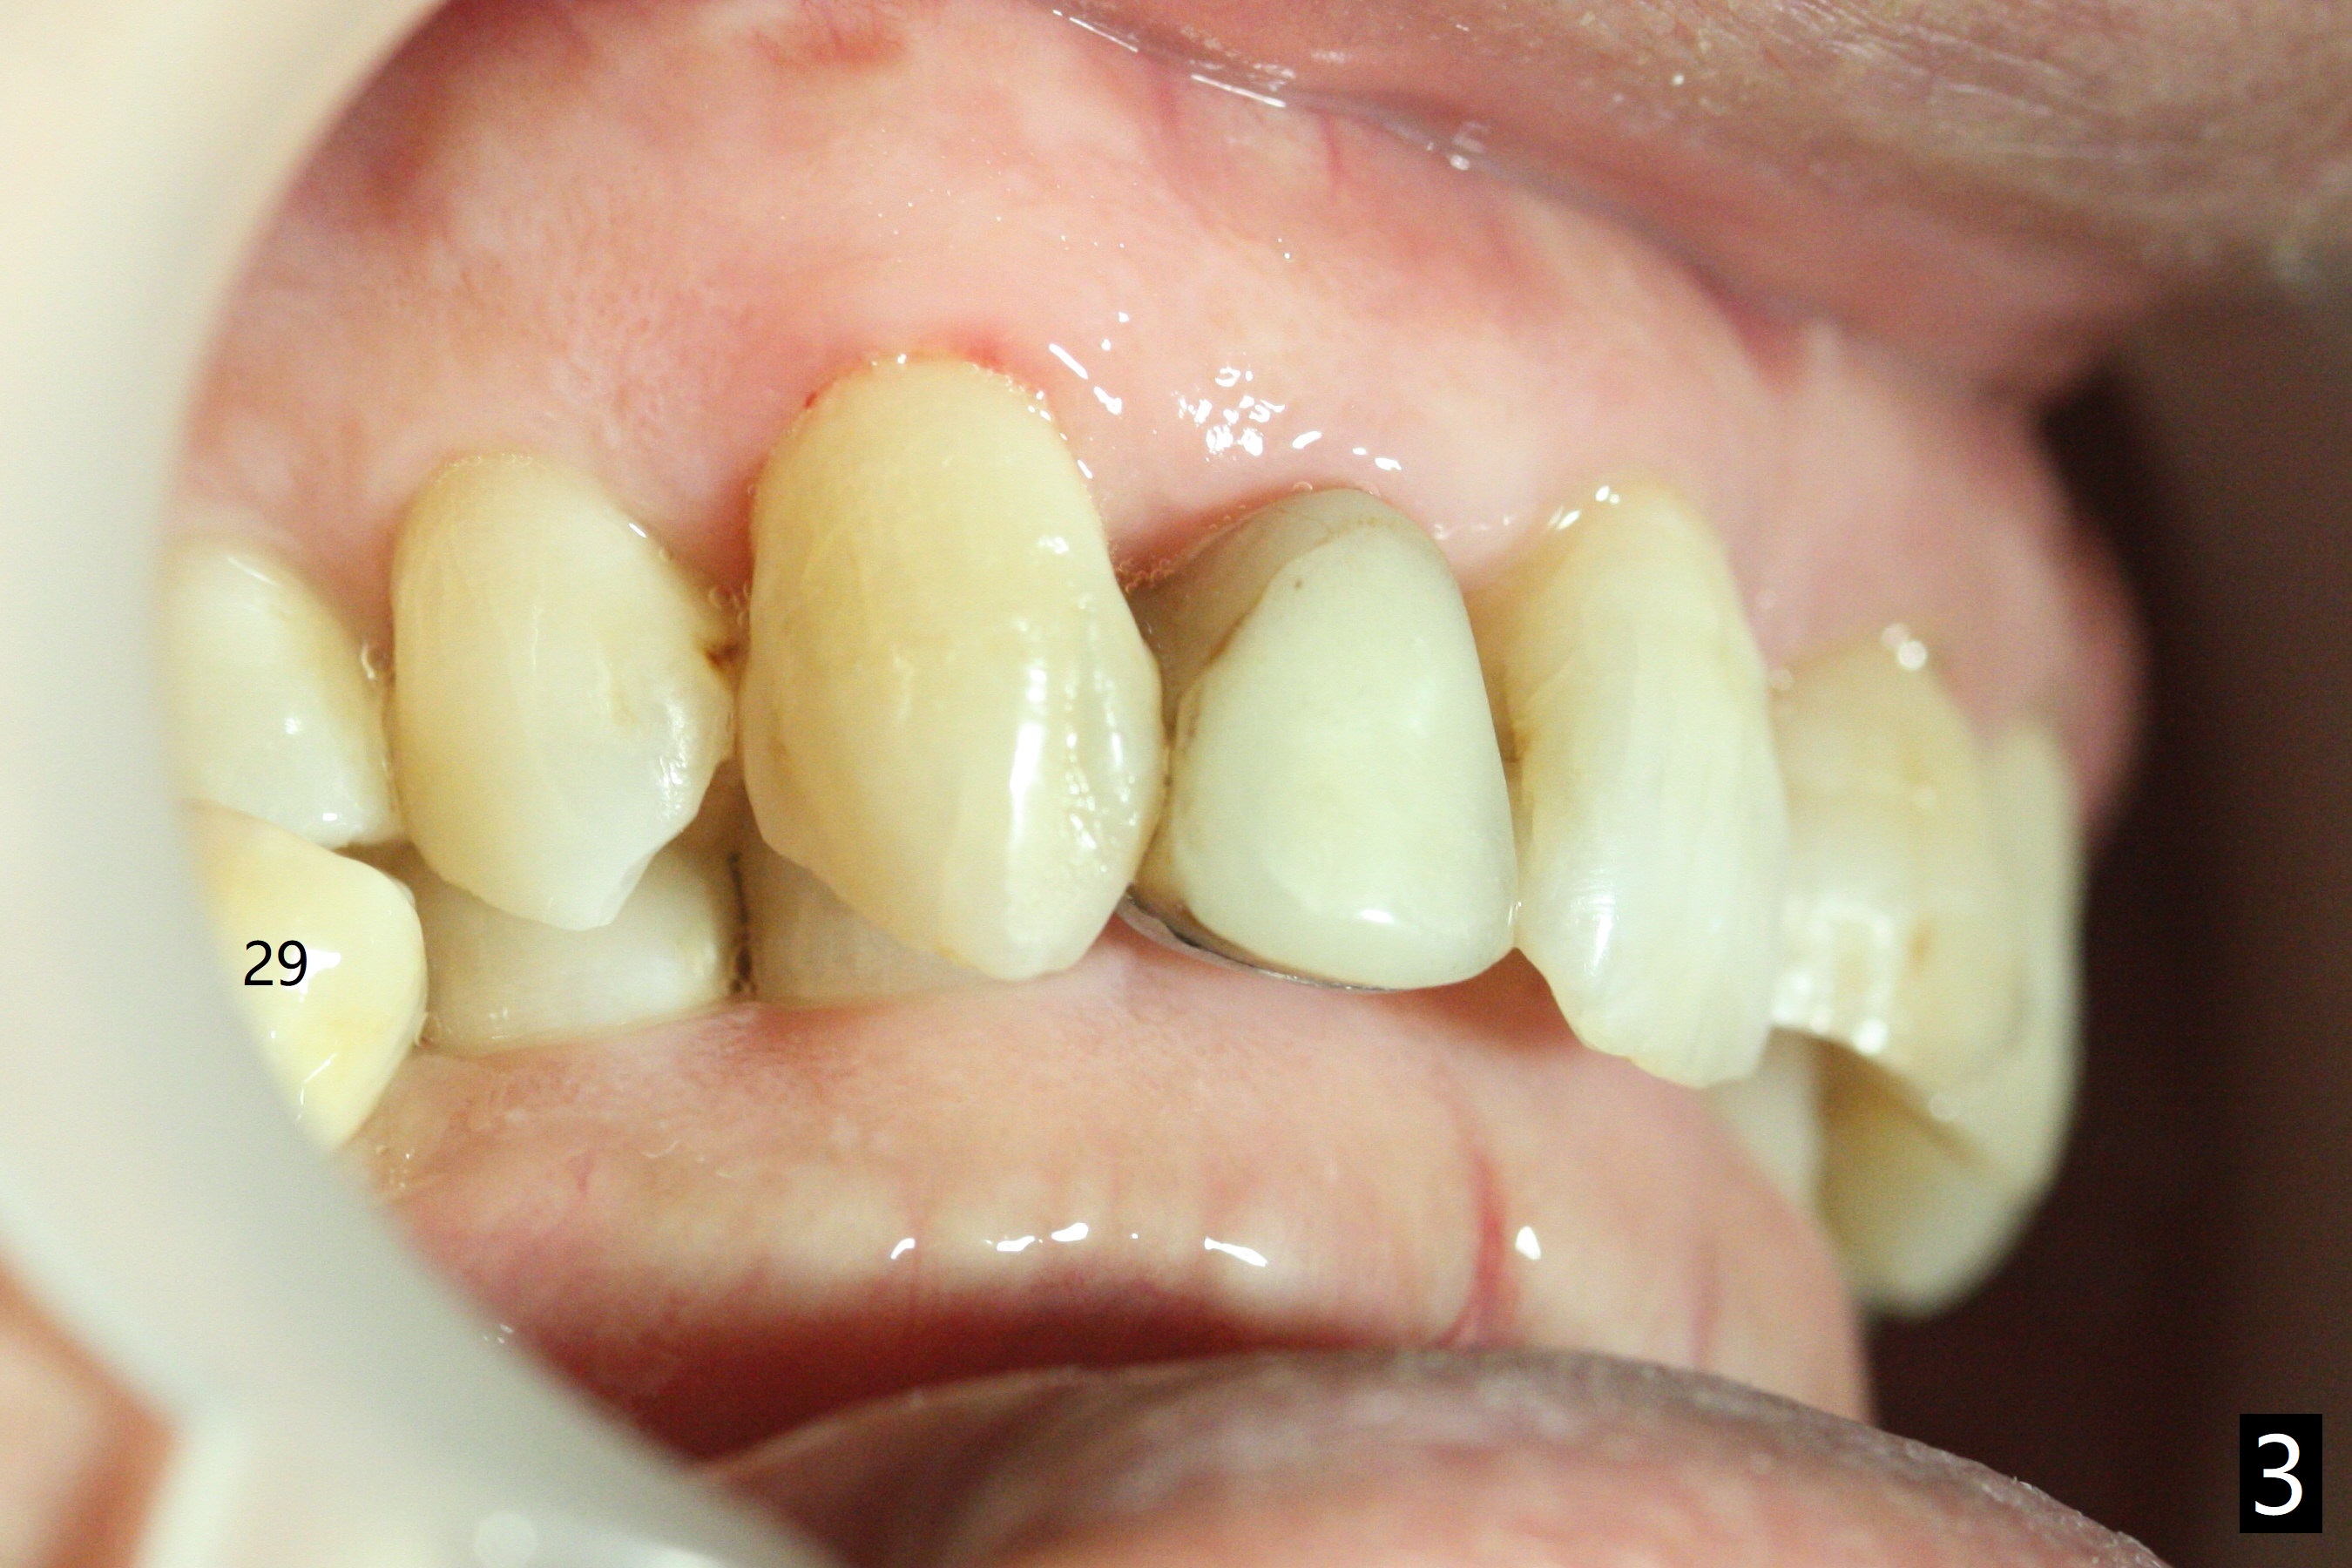

A 61-year-old man presented to clinic for new patient examination last year (Fig.1). He was not interested in extraction and implant at #30 because of finance. This year he requested treatment since he cannot chew well (Fig.2). After exam, extraction and implant at #30 appear not to be a priority, since there is anterior deep bite (Fig.3) with posterior occlusal collapse (Fig.4) as well as #29 malposition.